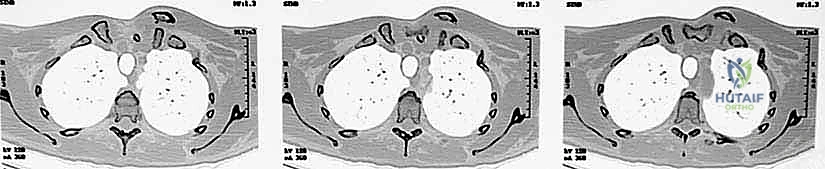

The absolute gold standard, and a non-negotiable prerequisite for surgical intervention, is a high-resolution Computed Tomography (CT) scan. The CT protocol must encompass both sternoclavicular joints and the medial halves of both clavicles to allow for precise contralateral comparison. Axial, coronal, and sagittal reformats, along with 3D surface-rendered reconstructions, are essential. The CT scan definitively differentiates a true ligamentous dislocation from a medial physeal fracture, quantifies the exact degree and vector of displacement, and assesses the integrity of the articular surfaces.

Crucially, in the setting of a posterior dislocation, the CT scan must be performed with intravenous contrast. This "CT Angiogram" phase is vital to delineate the relationship of the displaced medial clavicle to the innominate vessels, the superior vena cava, and the aorta. It identifies pseudoaneurysms, intimal tears, or direct vascular compression that would mandate the immediate presence of a cardiothoracic or vascular surgeon during the exposure. The surgeon must template the anticipated drill hole trajectories for the reconstruction, ensuring they remain safely within the osseous confines of the manubrium and clavicle, directing the drill bit away from the mediastinum at all times.

Posterior dislocations, however, represent a true orthopedic emergency. The posterior displacement of the medial clavicle drives the bone directly into the superior mediastinum, placing a dense network of vital neurovascular and visceral structures at immediate risk. Up to 30% of patients with posterior SC joint dislocations will present with symptoms of mediastinal compression. These symptoms can range from venous congestion and diminished ipsilateral upper extremity pulses to severe dyspnea, dysphagia, dysphonia, or a choking sensation. The potential for catastrophic injury to the brachiocephalic vessels, trachea, and esophagus mandates a high index of suspicion, rapid diagnostic evaluation, and urgent, definitive management.